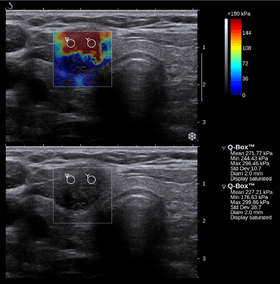

Nowadays, the medical imaging modality of elastography can also be used to determine the stiffness of tissues. Manual palpation suffers from several important limitations: it is limited to tissues accessible to the physician's hand, it is distorted by any intervening tissue, and it is qualitative but not quantitative. Elastography is able to overcome many these challenges and improve on the benefits of palpation.

Elastography is a relatively new technology, and entered the clinic primarily in the last decade. The most prominent techniques use ultrasound or magnetic resonance imaging (MRI) to make both the stiffness map and an anatomical image for comparison.